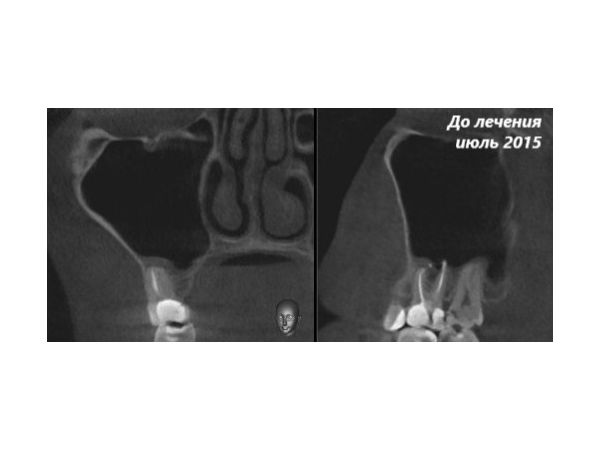

Пациент показал результаты КЛКТ, сделанные в период с лета 2015 года по весну 2016, которые хорошо отражали динамику развития периодонтита и изменений со стороны верхнечелюстного синуса в ответ на имеющийся в зубе очаг хронической инфекции.

КЛКТ за июль 2015 года (примерно через 9−10 месяцев после лечения пульпита зуба 1.6) показала:

- Тень пломбировочного материала в коронковой части зуба и в корневых каналах (запломбированы три из четырёх имеющихся в зубе корневых канала, во 2-м канале пломбировочного материала не было).

- Выведение небольшого количества пломбировочного материала за верхушку медиально-щёчного корня. Обращение щёчных корней в верхнечелюстной синус.

- Расширение периодонтальной связки рядом с медиально-щёчным корнем и утолщение слизистой верхнечелюстного синуса в пределах 2 мм.